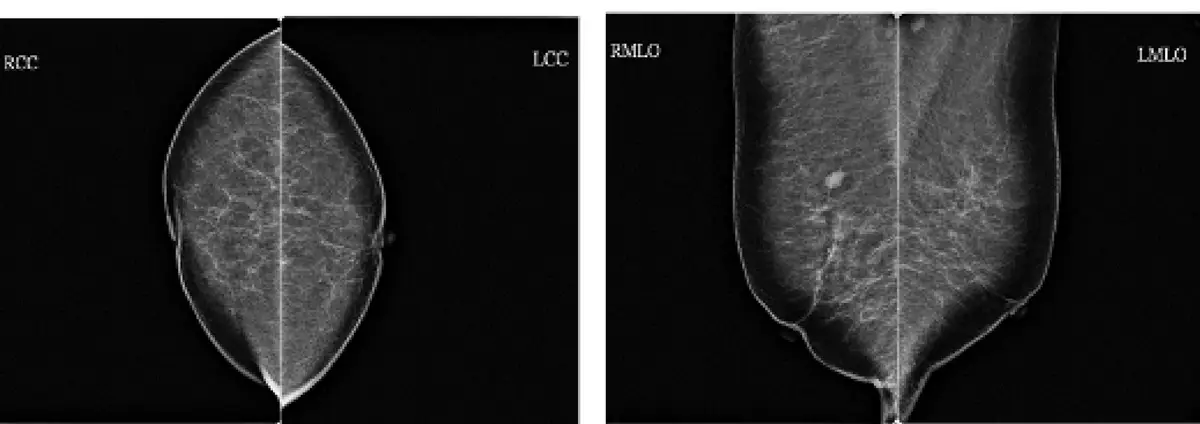

圖中顯示標準雙側乳房攝影(bilateral mammography)的四張影像,分為兩組:

左側一組(頭尾方向攝影,craniocaudal view, CC):

- RCC(右側 CC):右乳由上往下投照,顯示乳腺組織呈橢圓形分布,乳腺實質均勻分布

- LCC(左側 CC):左乳同方向投照,兩乳對稱呈現,可見乳腺組織密度分布情形

右側一組(內外斜位攝影,mediolateral oblique view, MLO):

- RMLO(右側 MLO):右乳斜位投照(約 45°),可見胸大肌(pectoralis major)邊緣、乳頭、腋尾部,呈特徵性的淚滴形

- LMLO(左側 MLO):左乳對應斜位,可見胸大肌邊緣清晰,乳腺組織完整包含

此四張影像(RCC、LCC、RMLO、LMLO)即為標準雙側乳房篩檢攝影的完整組合,每次篩檢共 4 張影像(每側 2 個投照方向)。